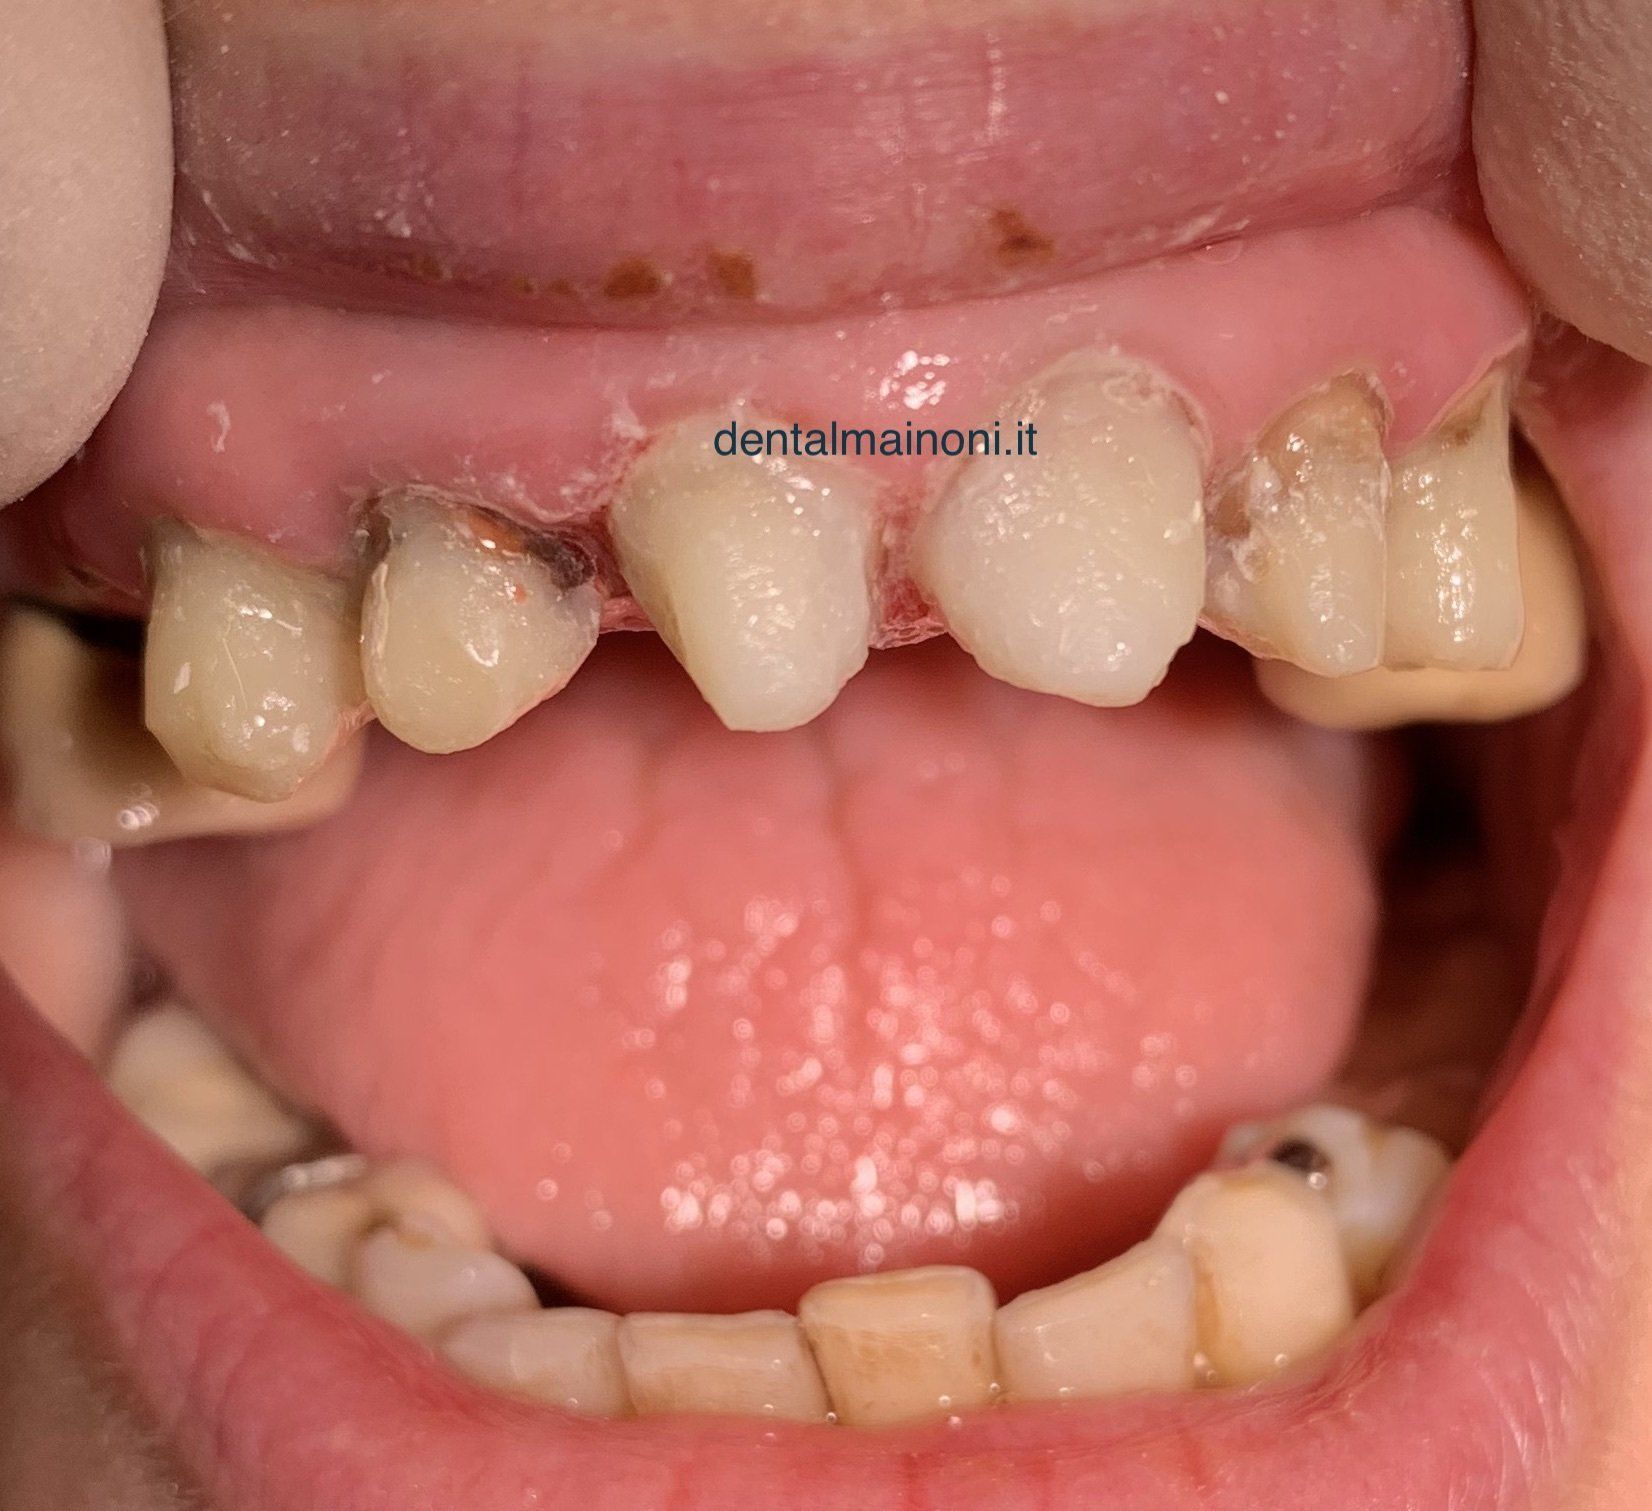

UN'EMERGENZA DENTALE / FOTO 3

ButtonSi procede alla ricostruzione dei monconi con perni in fibra e composito, dopo controllo con radiografia della correttezza delle devitalizzazioni delle radici.